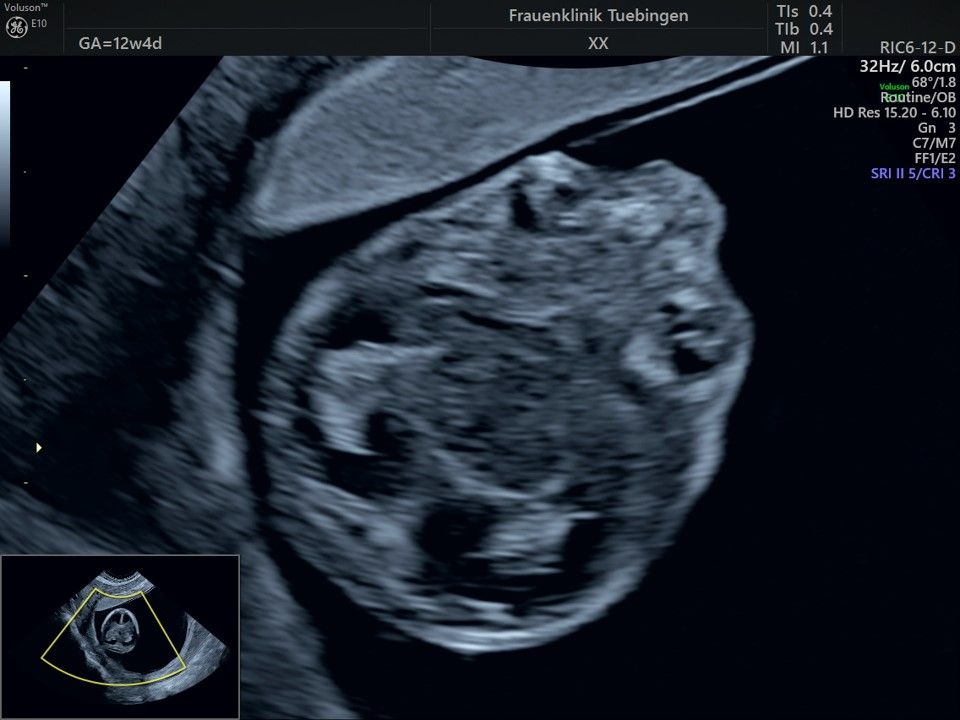

Bauchwanddefekt